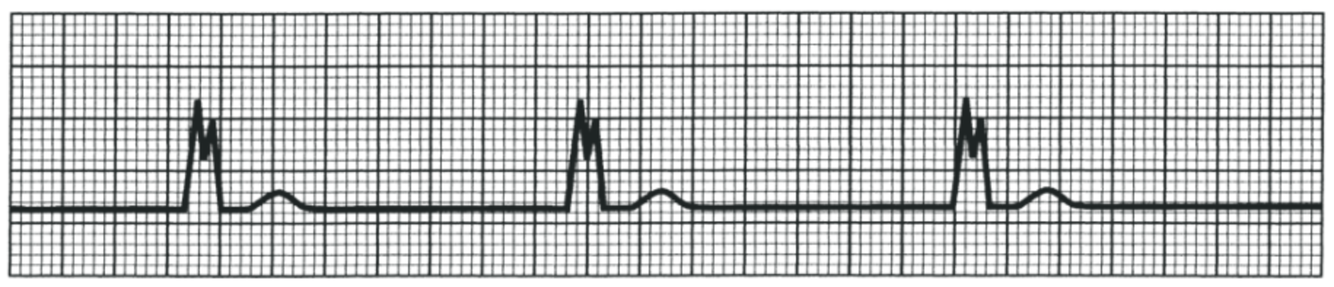

What is this?

2nd Degree AV Block - Mobitz Type II

QRS complex blocked without lengthening of PR interval

QRS wave can also be widened